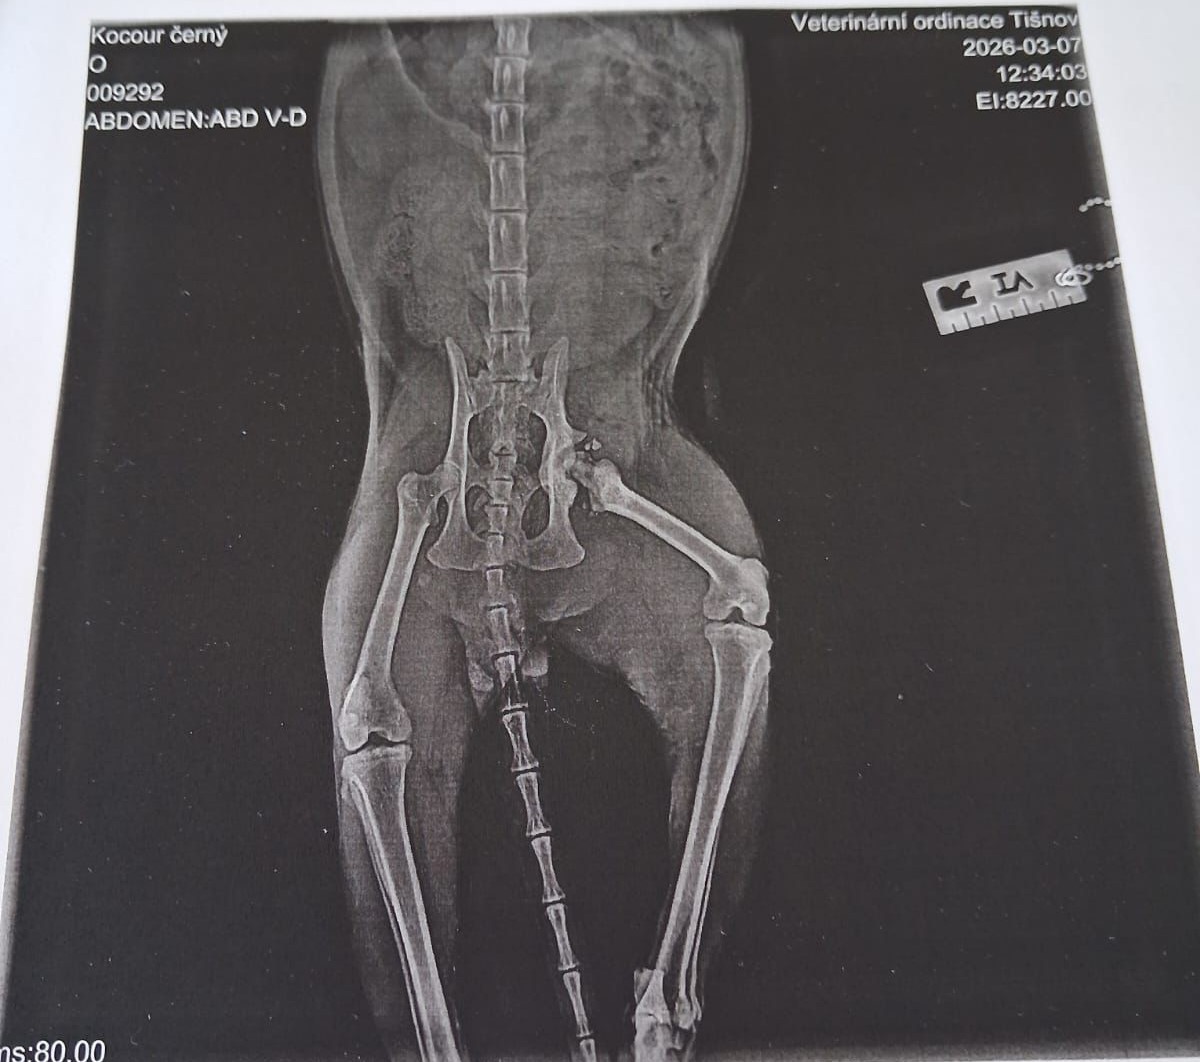

Rentgen však odhalil vážné poranění pravého kyčelního kloubu – hlavice stehenní kosti byla vykloubená a v okolí kloubu se nacházely úlomky kostí. Evan musel zůstat hospitalizovaný a podstoupil operaci.